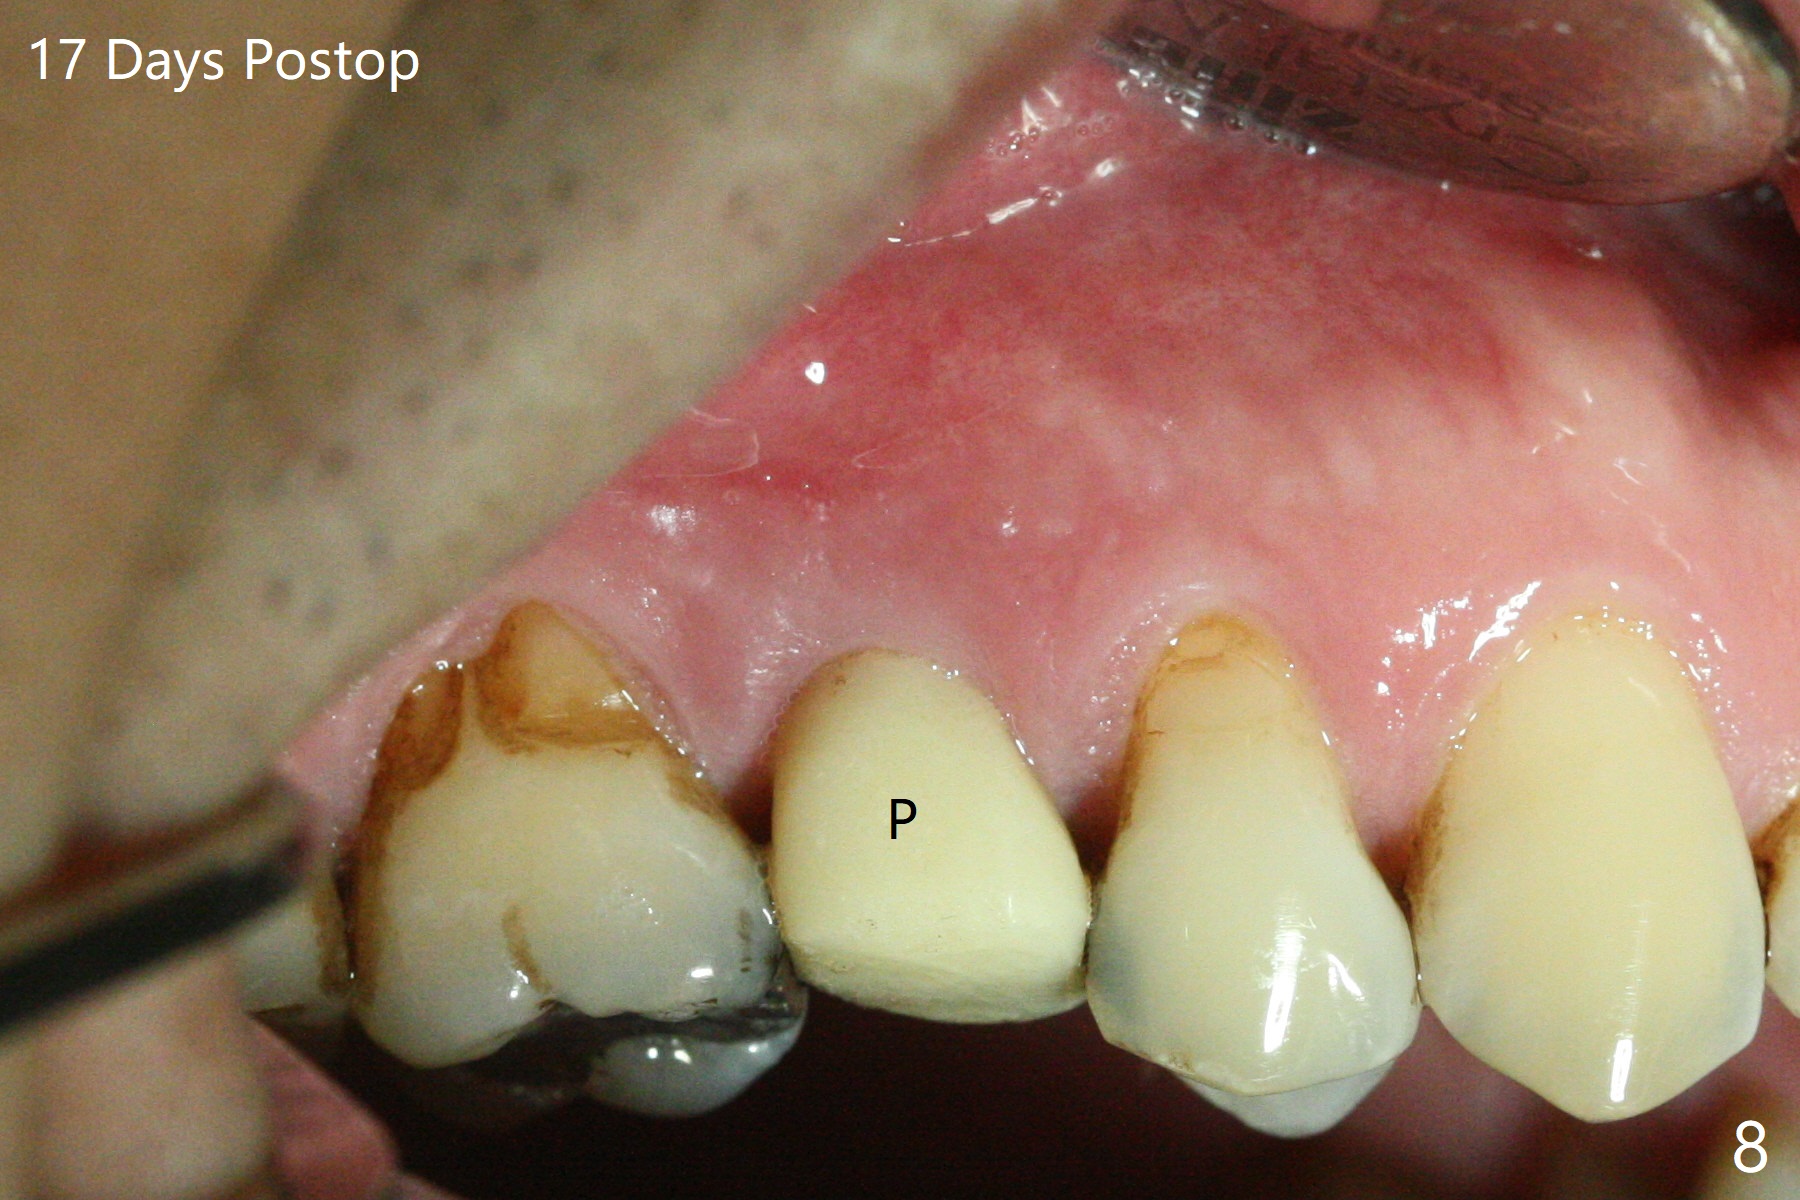

The 48-year-old man agrees to extract the tooth #4 with buccal and palatal fistulae (Fig.1,2 >) and large PARL (Fig.3 *) because of purulent discharge. The large post (Fig.3 P) is most likely associated with a longitudinal fracture. The latter is not noted until postop (Fig.4 <). Intraop finding is large amount of granulation tissue removed from the mesial apical region (Fig.3,5 *). With 10.5 mm offset, Sinus Approach Drill (19 mm) is estimated too short for sinus lift after 3x8.5 mm drill. Without careful repeated check, 2.2x10 and 2.2x11.5 mm drills are used. The sinus floor is perforated, but the membrane seems to be intact. The perforation is too small to insert PRF, but alright for allograft. Then nose blowing test shows that the sinus membrane is perforated, which seems to be repaired after placement of 2 pieces of PRF membrane, followed by another round of allograft (Fig.5 G), which is lifted by a 4x10 mm IS dummy implant. Before placement of a 4.5x11.5 mm final UF implant, allograft is placed in the 3 defective bony areas mentioned above, including the apical mesial one (Fig.6 *). But the final UF implant seems too short with non-satisfactory torque. The latter appears to be solved with the increased length of the implant (Fig.7). The gingiva around the provisional (P) is healthy without fistulae buccal (Fig.8) or palatal 17 days postop (Fig.9). A new abutment with 1 mm longer cuff is seated completely 5.5 months postop (Fig.10 < (no gap), as compared to Fig.7). The lower portion of the mesial defect seems to have been repaired (Fig.11 arrow, as compared to Fig.7). The bone in the sinus seems stable 1.5 years postop (Fig.12). There is no crestal bone loss 4 months post cementation (Fig.13). Return to Upper Premolar Immediate Implant, Trajectory II Xin Wei, DDS, PhD, MS 1st edition 09/27/2019, last revision 04/12/2021